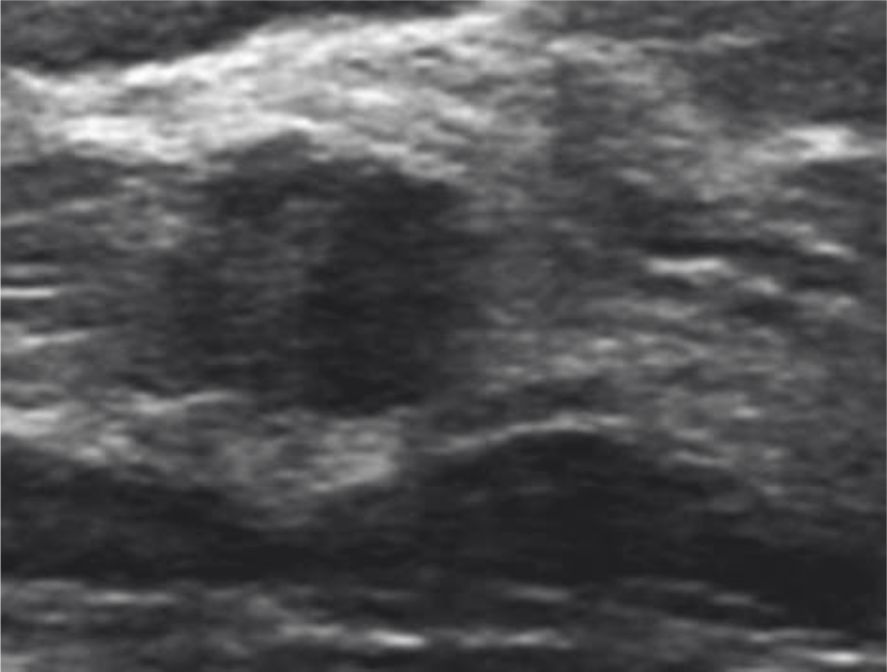

En ultrasonido el 100% de los hallazgos fueron nódulos

sospechosos, (Figura1,2)

Figura 1

Ecografía de alta resolución. Muestra un nódulo

sólido, hipoecoico de 8 mm de diámetro, de

márgenes microlobulados categorizados como ACR

BI-RADS® 4B. Histología Carcinoma Invasivo de Tipo

No Específico (NOS).

Figura 2

Nódulo sólido, ovoideo de contornos

circunscritos con extensión intraductal

categorizado como ACR BI-RADS® 4B.

Histología Fibroadenoma